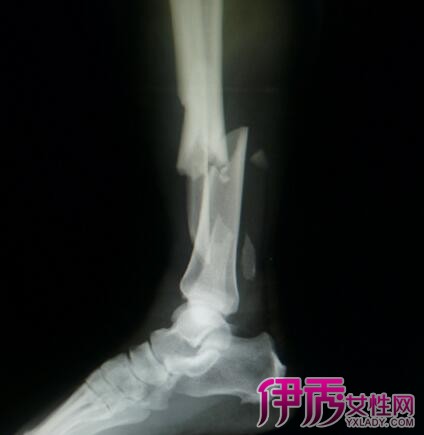

小腿粉碎性骨折属于几级伤残?如果你是在工伤中受伤,可以鉴定为九级伤残,享受本人九个月的工资补偿。如果你是在交通中受到了事故损伤,可以鉴定为二级伤残,享受伤残补助。如果是人身损伤,则可以鉴定为八级伤残。采用正确的治疗,是不会有任何后遗症的。治疗骨折的关键,不是固定,手术和石膏都是固定,不是治疗。治疗是用药物促使骨折处尽快的长出骨痂,达到彻底康复,这才是治疗的重点,而不是静养吃补品,靠静养饮食来帮助骨头生长,作用是非常小的,快则3个月痊愈,慢则6个月痊愈,不过也有些一年都没有彻底痊愈的。具体多久能愈合,这都是因人而异。不管是什么组织损伤,治疗的道理都是让损伤的组织快速生长就可以愈合,治疗的重点不是静养自身慢慢恢复,而是让其快速生长。只有让断骨在短时间内生长愈合,这才是治疗的重点。要想断骨快速愈合康复,建议选用传统中医治疗,中医治疗普通骨折,只需简单手法复位再用夹板体外固定,之后关键是用中药进行外敷快速接骨,用药7天左右疼痛可以基本消除,肿的现象也会随之消退,用药12天左右可以拆下夹板,大约用药30天左右可以基本恢复正常生活活动。